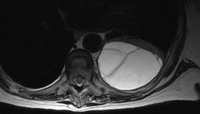

MRI scan of septated empyema

From the collection of Najib Rahman, RTU, Oxford